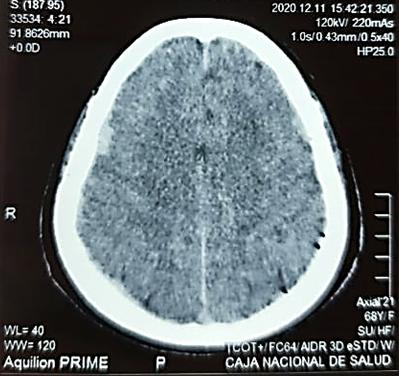

Paciente masculino de 17 años, acude a la clínica Odontológica de la Universidad Privada del Valle en La Paz, con el motivo de consulta y solicitud de revisión integral de piezas dentarias asintomáticas al momento de la revisión, así mismo refiere unión de dos piezas dentaria en el sextante anterosuperior por lo que requiere valoración y tratamiento respectivo. En la historia medica no se evidencia patologías de relevancia para el caso.

Al examen clínico intraoral se evidenció en la pieza, motivo de consulta, una alteración del desarrollo

dentario de forma, asemejando tener dos coronas en una sola pieza dentaria, unidas parcialmente en el tercio medio y cervical, delimitado por un surco central proveniente de la unión cementoesmalte, presentando una corona disto vestibular y otra mesiopalatina, hacia el borde incisal las coronas están separadas, también se evidencia a nivel del surco una caries de esmalte con cambio de coloración marrón (Fig. 1.A). A nivel de la cara palatina de la pieza 1.2 se evidencia la presencia de una cúspide accesoria en la corona mesiopalatina la misma que se denomina cúspide en garra (Fig. 1.B).

RIIS UNIVALLE. Ene-Jun. 17(42), 2022; ISSN: 2075-6208 25

Strauss-Quintela M. y cols.

Endodoncia y rehabilitación protésica como alternativa terapéutica de geminación dental

Figura Nº1 A. Fotografía intraoral en oclusión, señalando la pieza (1.2) note el surco vestibular con cambio de coloración. B. Fotografía intraoral oclusal se observa en la corona mesiopalatina la cúspide en garra.

Fuente: Elaboración propia, octubre 2021.

Se solicita una radiografía periapical, en la misma se observa la presencia del conducto radicular único, ancho con una sola cámara pulpar, está misma

ubicada en la corona mesiopalatina, también se puede observar la imagen radiopaca que evidencia la cúspide en garra (Fig.2).

Figura Nº2. Radiografía periapical que muestra que la pieza dentaria presenta una sola raíz y un solo conducto radicular, además presenta la imagen radiopaca de la cúspide en garra.

Fuente: Elaboración propia, septiembre 2021.